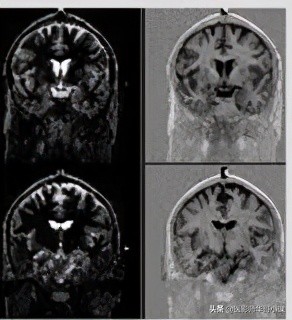

模图采集,只关心矢量的大小,不关心其方向(即是正矢量还是负矢量),那么对应到灰阶时就是,量的绝对值越大,越白;绝对值越小(即越接近于零矢量),越黑。我们对照模图M来看,在脑白质过零时采集,那么由于脂肪比脑白质弛豫快,那么其矢量已经恢复到正方向且有较大的值 ,在M图上表现为较高信号(亮);脑灰质由于比脑白质弛豫慢,那么采集时其仍在恢复,但其还没有达到零,仍有较少的负矢量,那么在M图上表现为稍高信号(灰);脑脊液由于拥有很长的T1值,那么其弛豫是非常慢的,采集时,其仍拥有很大的负矢量,那么在M图上就表现为高信号(亮);但由于采集时脑白质刚过零,那么其矢量为零,在M图像上就对应最黑,跟空气差不多(背景是黑色),即无信号。

实图采集,不仅关心矢量的大小,也关心其方向(即是正矢量还是负矢量),那么对应到灰阶时就是,最大正矢量对应最白;最大负矢量对应最黑,零矢量对应正中间的灰色,即背景为灰色(空气是没有信号的)。我们对照实图R来看,在脑白质过零时采集,那么由于脂肪比脑白质弛豫快,那么其矢量已经恢复到正方向且有较大的值,在R图上表现为较高信号对应到灰到白的灰阶,即亮白;脑灰质由于比脑白质弛豫慢,那么采集时其仍在恢复,但其还没有达到零,仍有较少的负矢量,那么在M图上表现为较低信号,对应着灰到黑的灰阶,即灰黑色;脑脊液由于拥有很长的T1值,那么其弛豫是非常慢的,采集时,其仍拥有很大的负矢量,那么在R图上就表现为更低的信号,趋于黑色;但由于采集时脑白质刚过零,那么其矢量为零,在R图像上就对应灰色,跟背景一个灰阶。